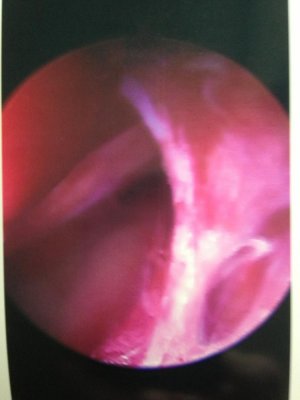

Here are a few pictures that the doc took while using the scope inside my shoulder.

He told me these were torn / frayed tendons and adhesions that were growing to lock my shoulder down in place. He was able to clean everything up and as soon as I finish healing I will be good to go.

I know it looks kind of gross, but I think it's totally amazing what they can do now with todays technology. Simply amazing.